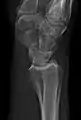

- Hip joint: AP and Lateral.[15]

- The Lauenstein projection a form of examination of the hip joint emphasizing the relationship of the femur to the acetabulum. The knee of the affected leg is flexed, and the thigh is drawn up to nearly a right angle. This is also called the frog-leg position.

AP view of normal hip

Lauenstein projection of normal hips

- Applications include X-ray of hip dysplasia.